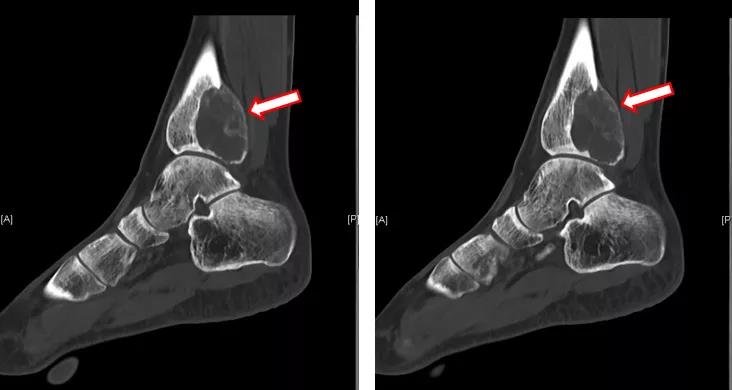

进一步完善CT检查提示:胫骨远端病变内不规则高密度影,成骨明显(图7~9)。

图7:左踝CT(地舒单抗治疗后)

图8:左踝CT(地舒单抗治疗后)

图9:左踝CT(地舒单抗治疗后)

术前应用地舒单抗三次(120mg,ih,q1w),疗效显著,复查MRI提示胫骨远端病变内T2WI高信号范围减小;CT提示病变内不规则高密度影,成骨明显。